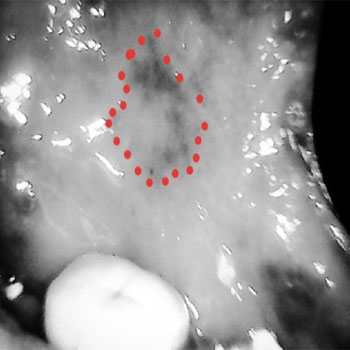

The narrow and mini head of the device can be inserted in to the oral cavity even in restricted mouth opening conditions such as OSMF and Squamous cell carcinomas to allow better visualization even in hidden areas of the oral cavity.

Lesion in Retro molar region with other oral cancer screening devices with larger head and extra oral imaging

The HD camera with 5MP will enables visualizations more clearly

Image of the lesion after filtering with smaller head and camera in the device after filtering.

same lesion with the camera in the device with low intensity of light